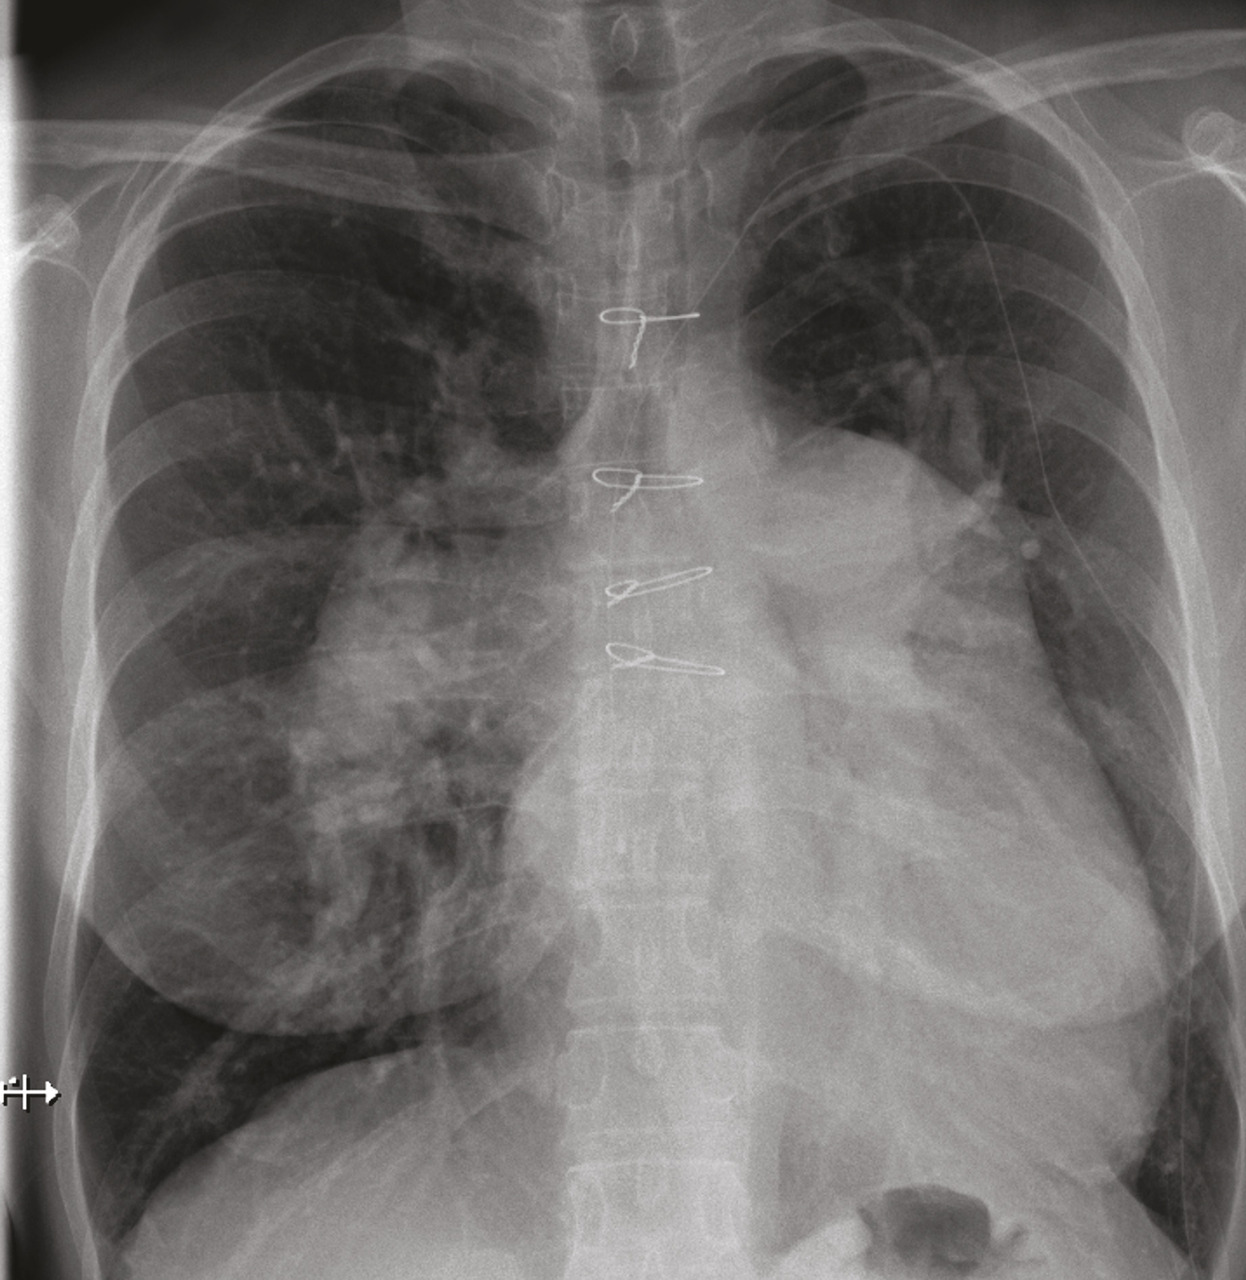

Les marqueurs cardiaques tels que le BNP (Brain natriuretic peptide) et/ou le NT-proBNP (N-terminal pro-brain natriuretic peptide) peuvent être augmentés en cas d’HTP. Ces biomarqueurs sanguins sont également utilisés dans le cadre du suivi des patients atteints d’HTP, une fois le diagnostic confirmé.Radiographie thoracique

La radiographie thoracique montre généralement une dilatation des artères pulmonaires proximales et un élargissement des cavités cardiaques droites (oreillette et ventricule droit) [Épreuves fonctionnelles respiratoires

fig. 3 ]. Elle permet aussi de rechercher des anomalies parenchymateuses témoignant d’une maladie respiratoire associée (emphysème, fibrose pulmonaire, etc.), d’une maladie veino-occlusive ou encore d’une origine post-capillaire.1,2